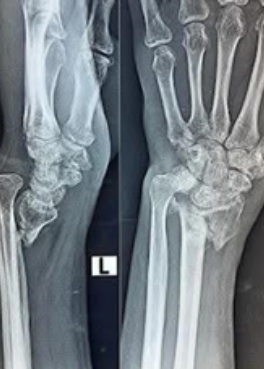

Hand and Upper Limb Specialist

Dr Melanie Amarasooriya is an internationally recognised Sri Lankan trained board-certified Consultant Orthopaedic Surgeon with advanced subspecialty training in the United Kingdom and Australia. In addition to trauma and general orthopaedic practice, she is a fellowship-trained Hand and Upper Limb Surgeon with expertise in hand, wrist, and elbow surgery. She provides comprehensive care through both surgical and non-surgical treatment approaches tailored to patient’s individual needs.